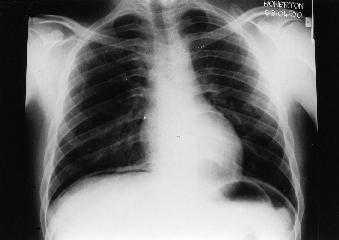

结合下面的病史和X线影像,考虑患者最可能的诊断是()

病史:患者男性,61岁,突发上腹痛7小时。

诊断:消化道穿孔图解:立位腹平片示双侧膈肌光滑,膈下可见新月形透亮的气体影。腹部肠管未见扩张及气液平。

消化道穿孔常继发于胃肠道溃疡、创伤破裂、炎症及肿瘤,其中胃、十二指肠溃疡穿孔最为常见。

胃肠道穿孔表现有气腹、腹腔积液、腹脂线异常和麻痹性肠胀气,其中以游离气腹最重要且出现较旱早。腹腔内游离气体可上浮到横膈与肝或胃之间,立位片表现为一侧或双侧膈下透亮的线条状或新月形气体影;气体可进入小网膜囊。在中腹部腰椎右侧见气腔或气液腔;气体可进入腹膜后间隙,衬托出肾脏的外形轮廓。